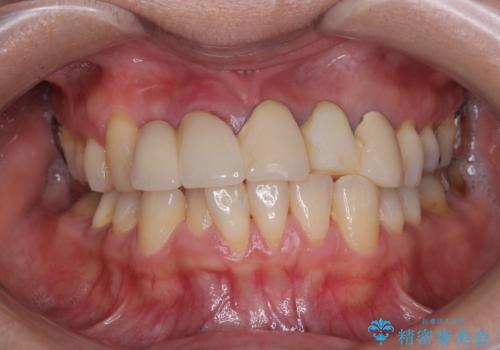

不具合の多い前歯 オールセラミックブリッジ治療

- 前歯のブリッジに違和感を感じるとのことで来院された患者様です。

受け口を無理やりブリッジで改善したことで、支台歯の1本は歯根が破折しており抜歯が必要な状態でした。

根管治療がされている歯の一部には根尖部の違和感があり、根管治療が必要と判断されました。

抜歯および根管治療を実施した後にオールセラミッククラウンにて補綴することとしました。

歯肉ラインの改善には歯周外科処置が必要でしたが、大きく笑っても歯肉ラインが唇に隠れるとのことで、外見の改善はせず、清掃性の大会ブリッジを装着いたしました。